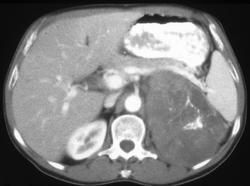

adrenal cortical carcinoma 肾上腺皮质: 肾上腺皮质癌 American Joint mittee on Cancer Staging; AJCC 美国癌症分期联合委员会 angiosara 血管内皮: 血管肉瘤 basal cell carcinoma 基底细胞: 基底细胞癌 calcitonin 抑钙素 car。